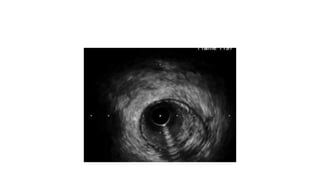

A 57-year-old woman was admitted to the hospital with chest pain. Electrocardiograms and troponin levels were normal. Intravascular ultrasound was performed before placing a stent in the left main coronary artery and left anterior descending artery to treat a blockage. The minimum lumen area increased to 4.24mm x 4.13mm after stenting.